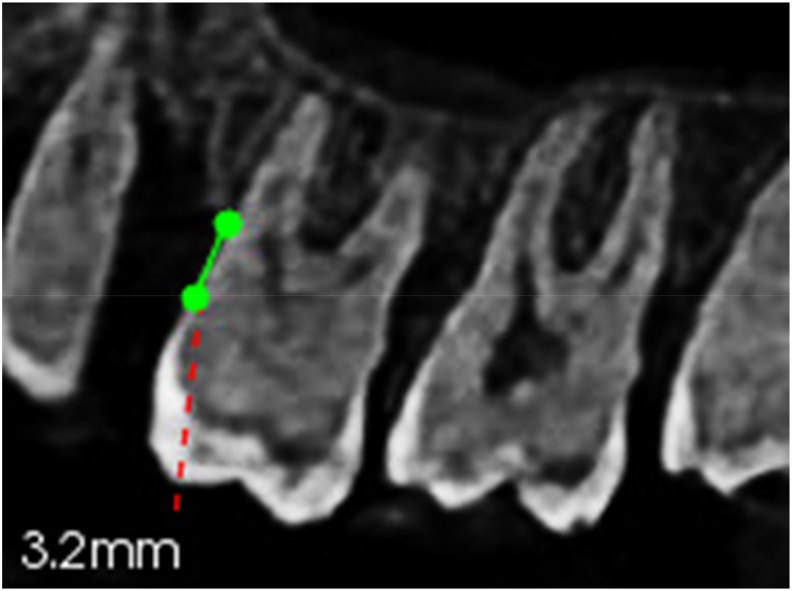

Abstract Image